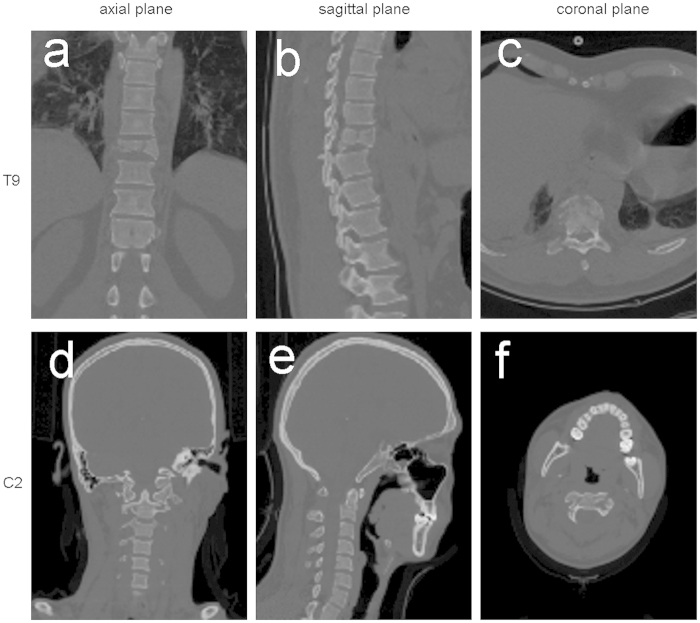

Students were randomized into three groups using a computer program. The TM of the first group (CT group) was based on the CT images of the two patients in sagittal, coronal, and axial planes (Fig. 2). The TM of the second group (3D group) was based on the 3D images reconstructed from the DICOM file, original data file from the two patients, each angle freely adjustable in the computer (Fig. 3 and S1,2 Video). In the last group (3Dp group), each student received the two fracture models (Fig. 4 and S3,4 Video). A teacher provided a detailed interpretation of the fracture in each group.

Figure 2. Screenshot of the teaching module for two-dimensional computed tomography images.

The ninth thoracic vertebra (T9):a, b, and c (axial, sagittal, coronal views, respectively); the second cervical vertebra (C2): d, e, and f (axial, sagittal, coronal views, respectively).